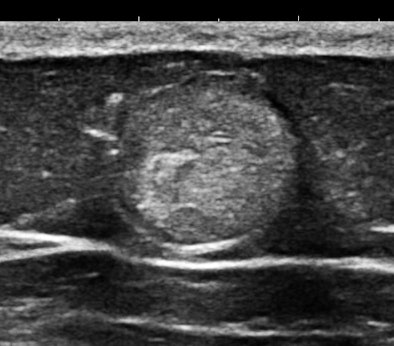

Of course, any of you might say that systemic mastocytosis is such a rare occurrence that one would probably never ever encounter one, but that is probably only true with fully and classically symptomatic cases. We have started looking at abdominal subcutaneous fat as part of our scanning routine, and guess what? This may not be such a rare occurrence at all. Here are some 15-MHz abdominal wall images of a 63-year-old hypothyroid woman who previously had a hysterectomy for a precancerous endometrial polyp:

Her history was interesting, with allergies that began in middle age and episodes of flushing during the past five years that she attributed to "hot flashes."

Soft, well-demarcated reflective nodules in subcutaneous fat are an Aunt Minnie of a sign. They are not palpable, and I suspect they can only be found by high-frequency ultrasound, which is perfect for outpatient screening applications. There may be a completely unexpected, relatively high prevalence of this finding, and it seems that multiple nodules may predispose several allergic disorders, including conditions such as irritable bowel syndrome (IBS), fibromyalgia, and possibly even exercise-induced asthma or postexertional hypotension and reactive tachycardia.

The first example is of an infiltrating, multifocal process, such as with leukemia; the second involves stable islands of cells without a supporting macrostructure; and the third is a solid, benign mass. The image features are distinct.